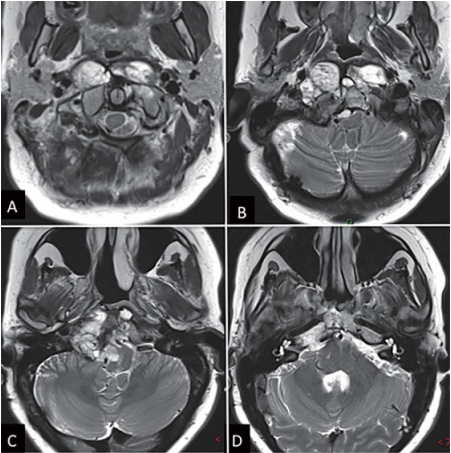

图1:内镜下鼻内镜入路前的术前影像。(A-D)MRI T2 WI显示一个巨大脊索瘤延伸至椎前间隙和齿状突周围。肿瘤横向延伸至舌下管和颈静脉孔,并向内侧延伸至硬膜内间隙。肿瘤从斜坡中部延伸至枢椎齿状突周围。